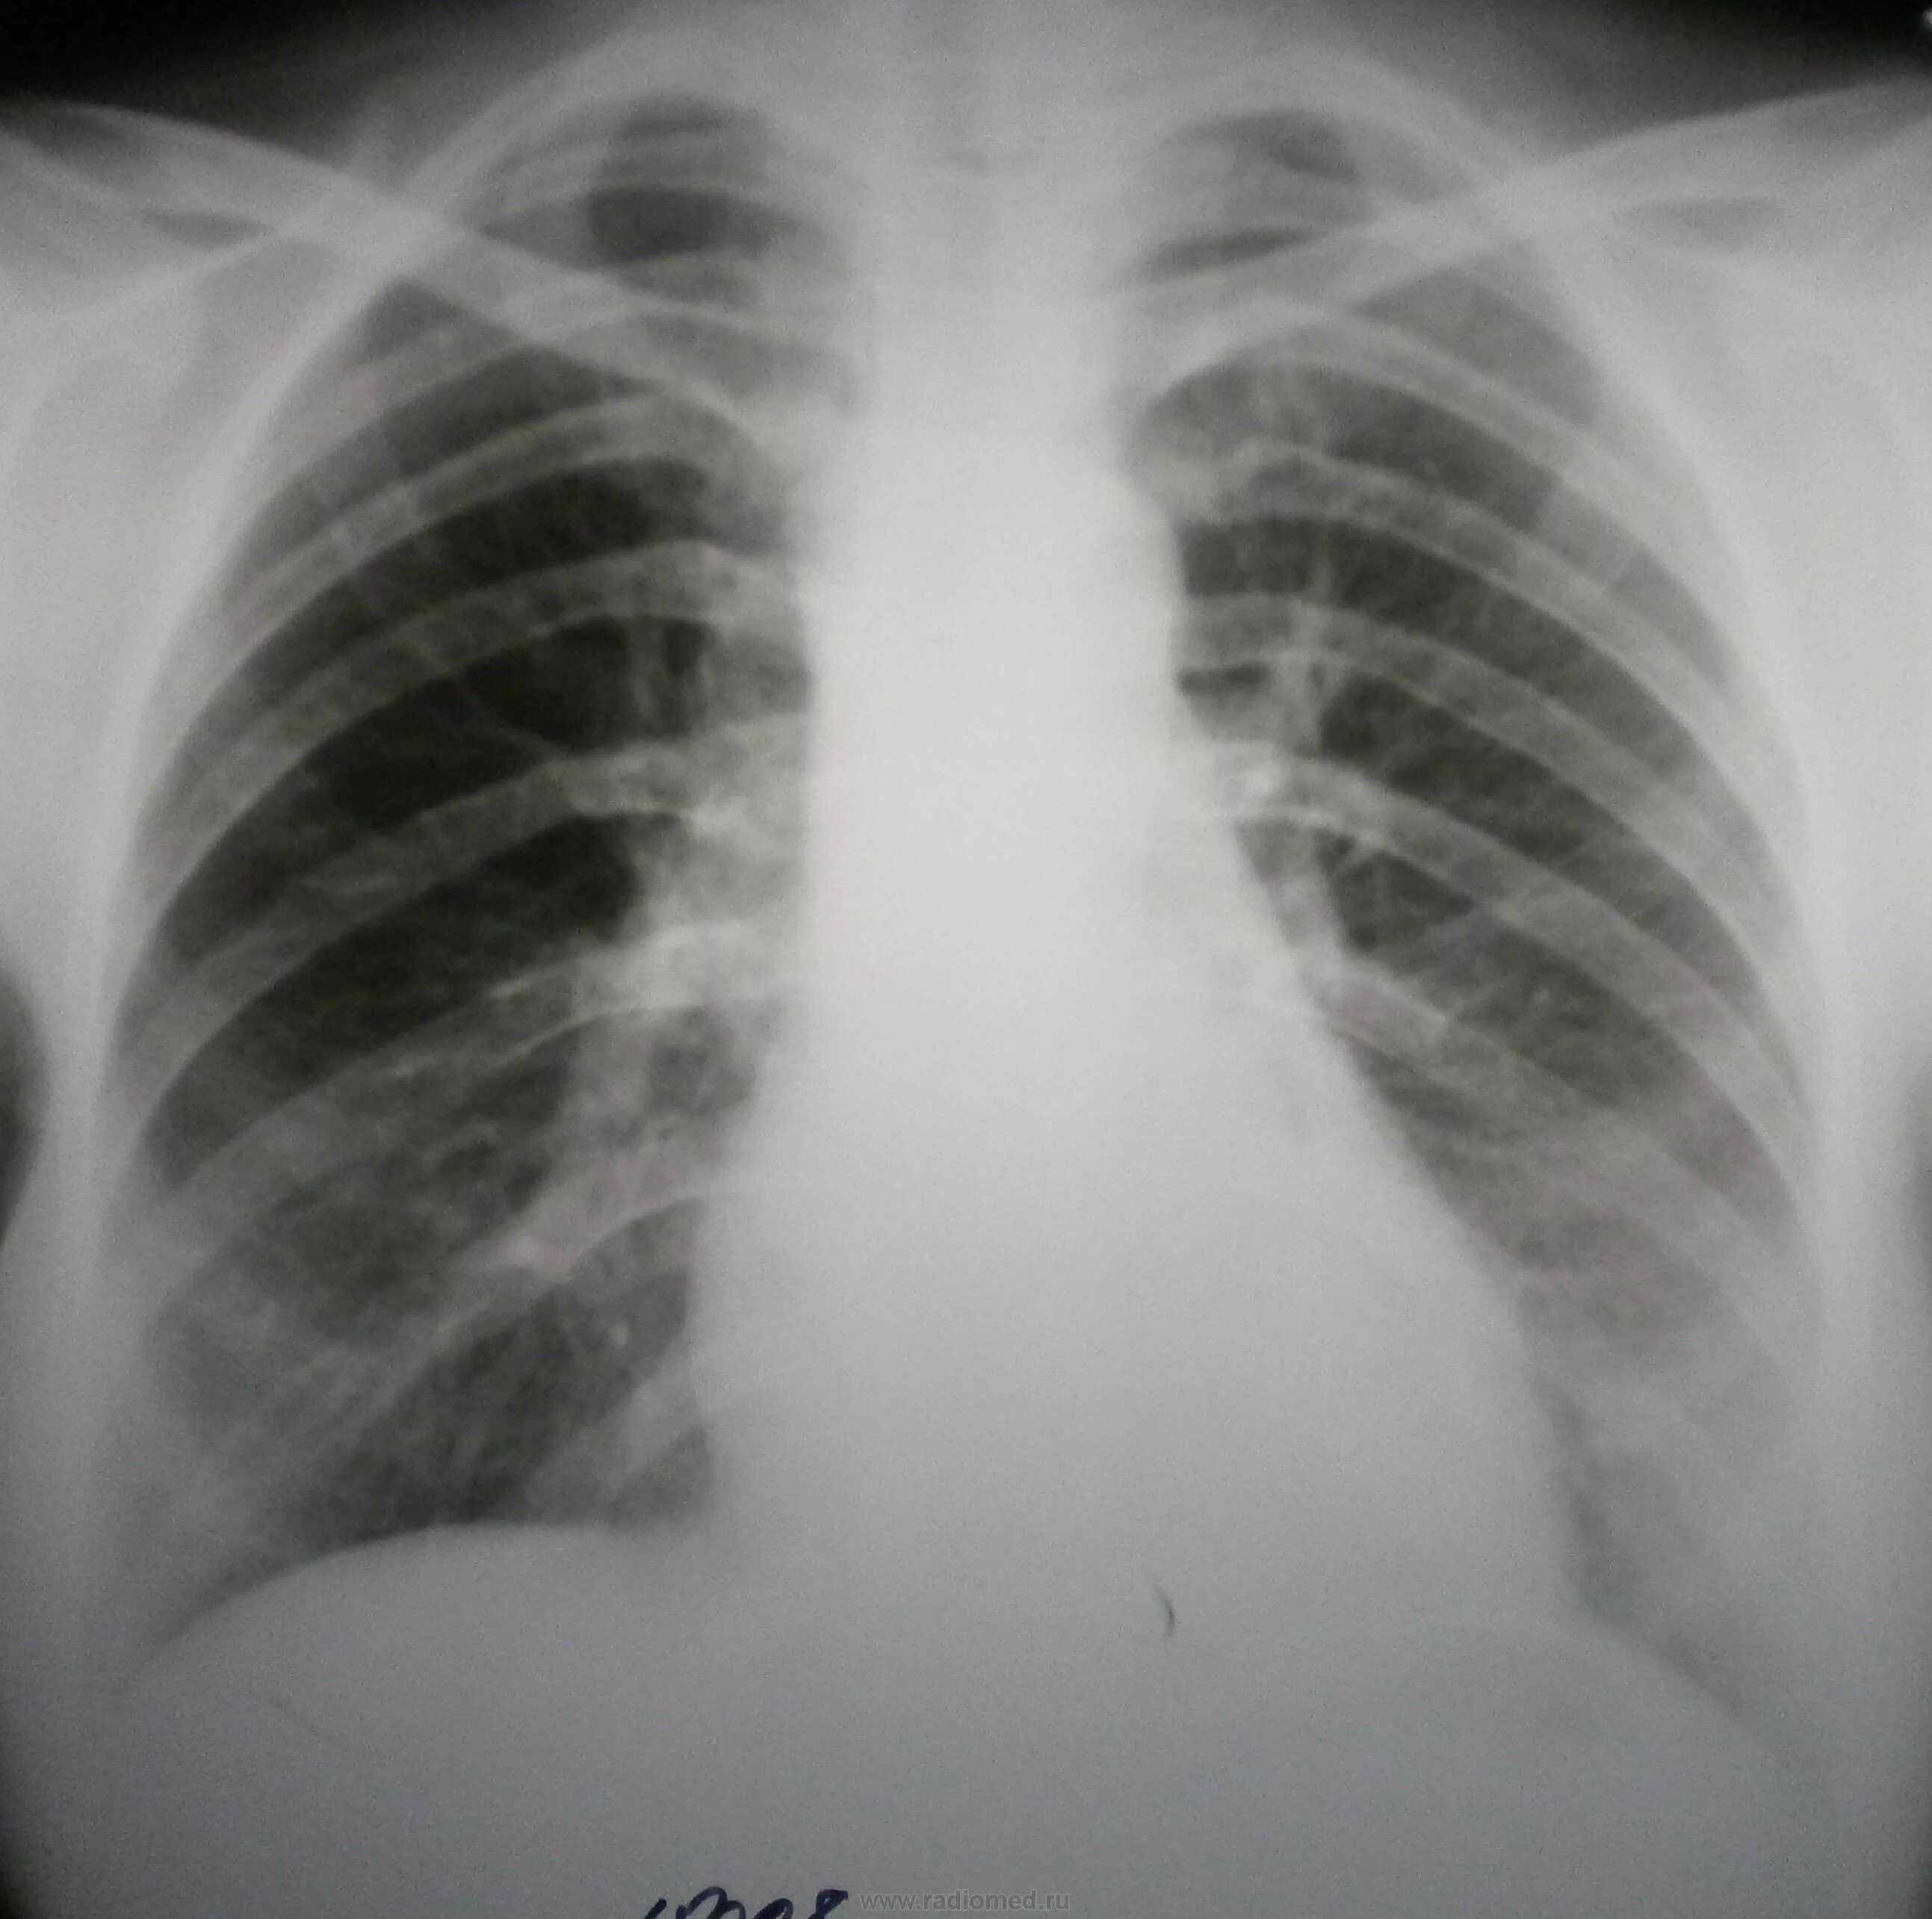

Медиастинит причины